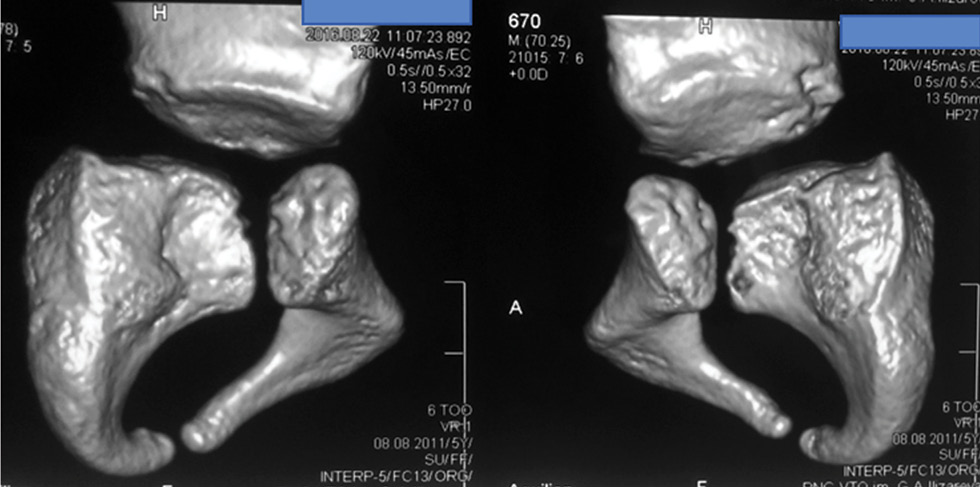

Рис. 3. Рентгенограмма таза и компьютерная томограмма пациентки В. до лечения: 3D-реконструкция впадин (правая и левая), показывающая в сравнительном аспекте степень левосторонней ацетабулярной дисплазии.

Fig. 3. X-ray of the pelvis and computed tomogram of patient V. before treatment: 3D reconstruction of the cavities (right and left), showing in a comparative aspect the degree of left-sided acetabular dysplasia.